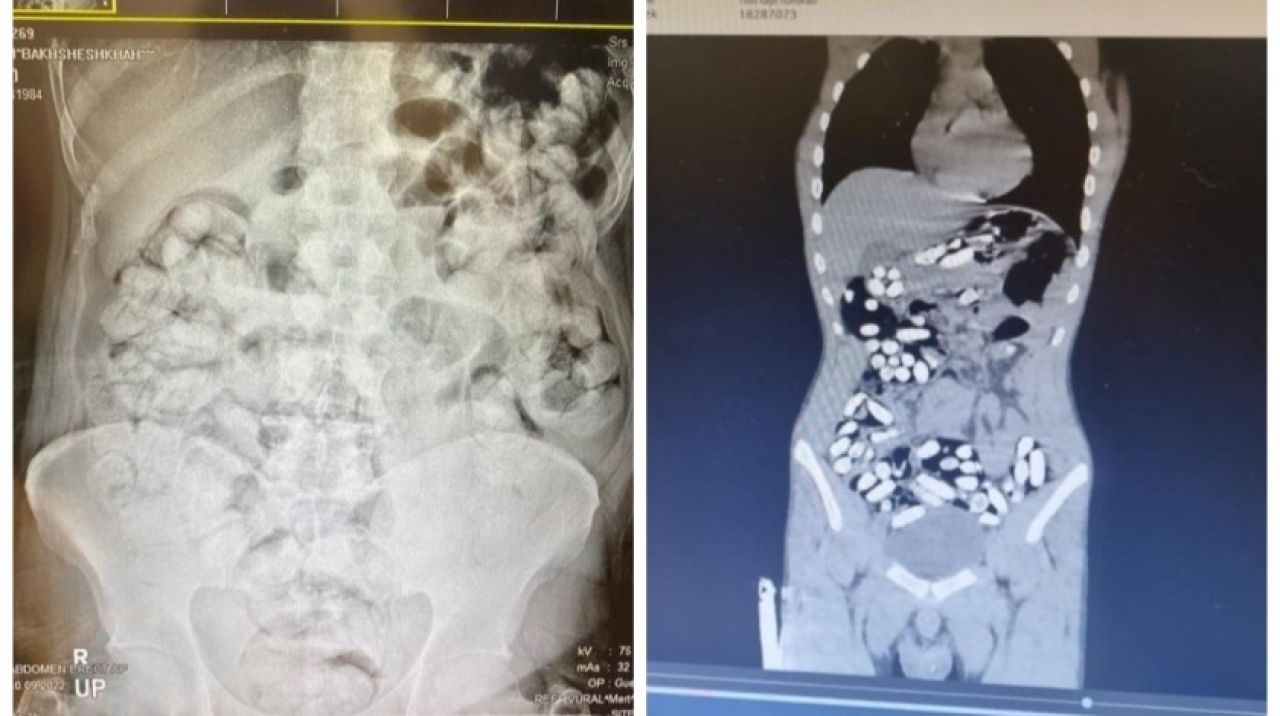

Çekilen röntgen filmlerinde şüphelilerin vücutlarında 62 kapsül eroin ve 210 kapsül afyon sakızı olduğu tespit edildi.

Röntgen çekimlerinde uyuşturucu kapsüllerinin şüphelilerin neredeyse iç organlarının her tarafına yayıldığı belirlendi. Doktor ve polis, vücutta tek seferde bu kadar yüklü miktarda uyuşturucu görmenin şaşkınlığını yaşadı. Gözetim altına alınan ve röntgenleri çekilen şüphelilerin vücudundan parça parça dışkılama yöntemi ile uyuşturucular çıkarıldı. Zanlıların hastanedeki işlemleri sürerken Narkotik Suçlarla Mücadele Şubesi ekiplerinin teknik ve fiziki takiplerinde, benzeri yöntemle yine aynı güzergahtan uyuşturucu götürüleceği bilgisi alındı. Bunun üzerine uygulama noktasında durdurulan bir otobüste, koltukta oturma şekilleri ile hal ve hareketlerinden şüphelenilen İran uyruklu Masoud T. ve Soleman O. gözaltına alınıp hastaneye götürüldü.

Yapılan kontrollerde ve röntgen çekimlerinde, şüphelilerin vücutlarından 411 kapsül afyon sakızı olduğu belirlendi. İlk operasyonda ve ikinci operasyonda yakalanan zanlıların, uyuşturucuları bugüne kadar rastlanılmayan kolonoskopi yöntemiyle vücutlarına soktukları değerlendirildi. Şüpheliler hastane kontrollerinde ise vücutlarına uyuşturucunun baygınken konulduğunu ve ne kadar miktarda uyuşturucunun vücutlarına doldurulduğunu bilmediklerini iddia etti. Doktor nezaretinde 5 gün süren dışkılama yöntemiyle vücutlarından 6 kilo 955 gram ağırlığında 683 kapsül uyuşturucu çıkartılan 5 şüpheli, emniyete götürüldü. Buradaki işlemlerinin ardından adliyeye çıkarılan zanlılar tutuklandı.